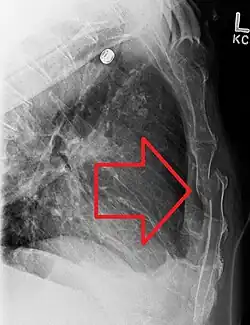

![]() | |

| A displaced sternal fracture as seen on plain X-ray | |